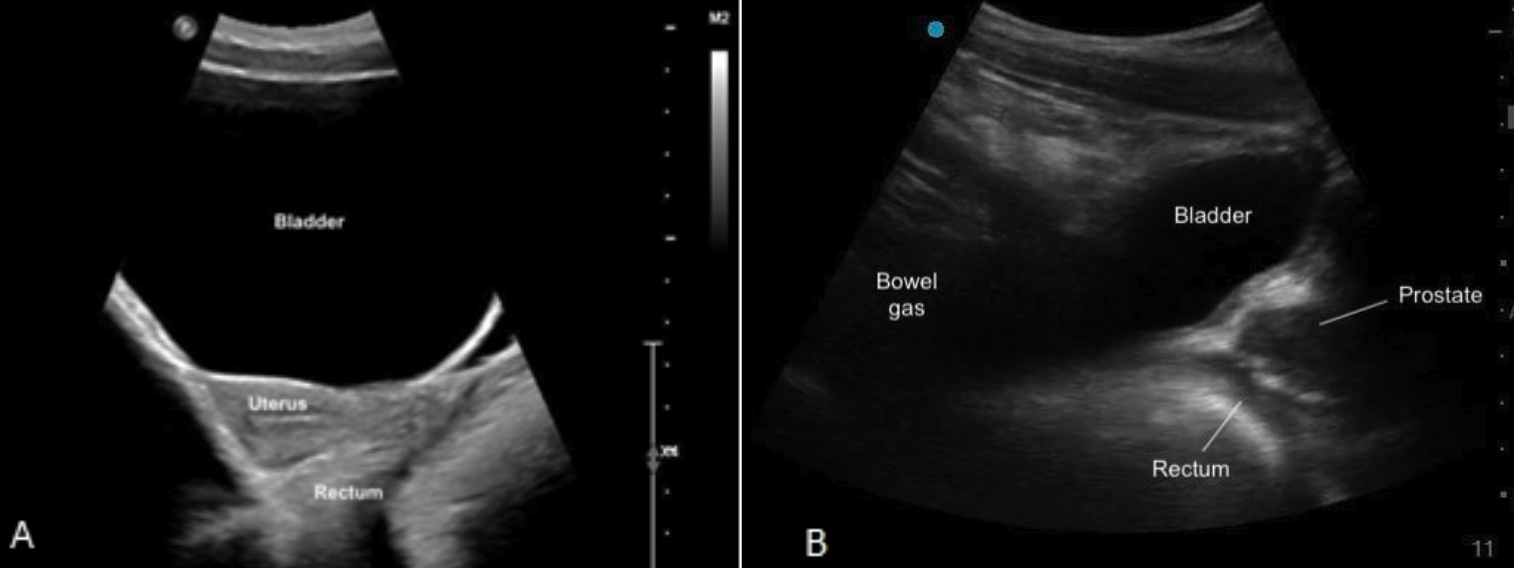

Parasternal Short Axis

Parasternal Short Axis (PSAX/PSSA)

The PSAX view provides a cross-sectional image of the ventricles, allowing simultaneous visualization of the RV and LV. For RV strain assessment, this view is useful for evaluating RV size, function. It is also the preferred view to assess the shape and position of the IVS.

The RV appears as a crescent-shaped structure anteriorly, wrapping around the circular LV cavity, with the septum forming a smooth, curved border between the two chambers (figure 8).

What is Normal?

• Crescent shaped

• Smaller than the LV

• In a normal PSAX view, the septum maintains a round, inward curvature toward the RV throughout the cardiac cycle.

Figure 7: Illustration of normal septal shape during systole and diastole in the PSAX view

Figure 8: PSAX view. Note how the septum maintains its round inward curvature during throughout the entire cardiac cycle and the crescent shape of the RV in the near field.

What is NOT Normal?

• Visually, if the RV is equal to or larger than the LV, then there is likely RV dilation. In severely dilated RVs, the LV will appear to look compressed by the RV

• Visually reduced contraction

• Septal flattening or becoming D-shaped when RV pressure > LV pressure

Septal Flattening

In the PSAX view, the LV will appear as a “D-shaped” structure. This is the result of RV volume overload (RVVO) or RV pressure overload (RVPO).

· In RVVO the septum is flattened only during diastole. This is the result of elevated RV volume filling at the expense of the LV, and causes the LV shape to deform by the end of diastole

· In RVPO the septum will be flattened throughout the entire cardiac cycle.

It is important to remember that to accurately assess septal position, the PSAX view should be obtained at the level of the papillary muscles, rather than at the mitral valve. At the mitral valve level, surrounding structures may artificially preserve septal shape despite significant RV loading.

It is also important to note that intra-cardiac shunts (e.g., VSDs) and arrhythmias can also limit the reliability of RV/LV and septal assessments in the PSAX view.

Figure 9: Illustration of Septal flattening or “D-sign” as seen in the PSAX view

Figure 10: PSAX view “D-sign” throughout cardiac cycle indicative of RVVO/RVPO